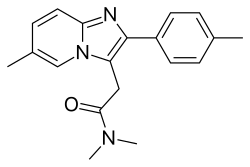

Nonbenzodiazepines

Nonbenzodiazepines, sometimes referred to as Z-drugs, are a class of hypnotic depressants that are mainly used to treat insomnia and sometimes anxiety.[128][129] They are structurally related to benzodiazepines. They positively modulate the benzodiazepine site of the GABAA receptor, the chief inhibitory receptor of the central nervous system, just like benzodiazepines, but at a molecular level, they are structurally unrelated.

Nonbenzodiazepines bind to the benzodiazepine at the GABAA receptor site to keep the chloride channel open.[130] This causes chloride in the intercellular area to flood into the neuron.[131] Since chloride has a negative charge, it causes the neuron to rest and cease firing. This results in a relaxing and depressant effect on the central nervous system.

Common nonbenzodiazepines like zolpidem and zopiclone are extremely effective for insomnia, but carry many risks and side effects. Sleeping pills, including zopiclone, have been associated with an increased risk of death.

Nonbenzodiazepines should not be discontinued abruptly if taken for more than a few weeks due to the risk of rebound withdrawal effects and acute withdrawal reactions, which may resemble those seen during benzodiazepine withdrawal. Treatment usually entails gradually reducing the dosage over a period of weeks or several months, depending on the individual, dosage, and length of time the drug has been taken. If this approach fails, a crossover to a benzodiazepine equivalent dose of a long-acting benzodiazepine (such as chlordiazepoxide or, more preferably, diazepam) can be tried, followed by a gradual reduction in dosage. In extreme cases and, in particular, where severe addiction and/or abuse are manifested, inpatient detoxification may be required, with flumazenil as a possible detoxification tool.